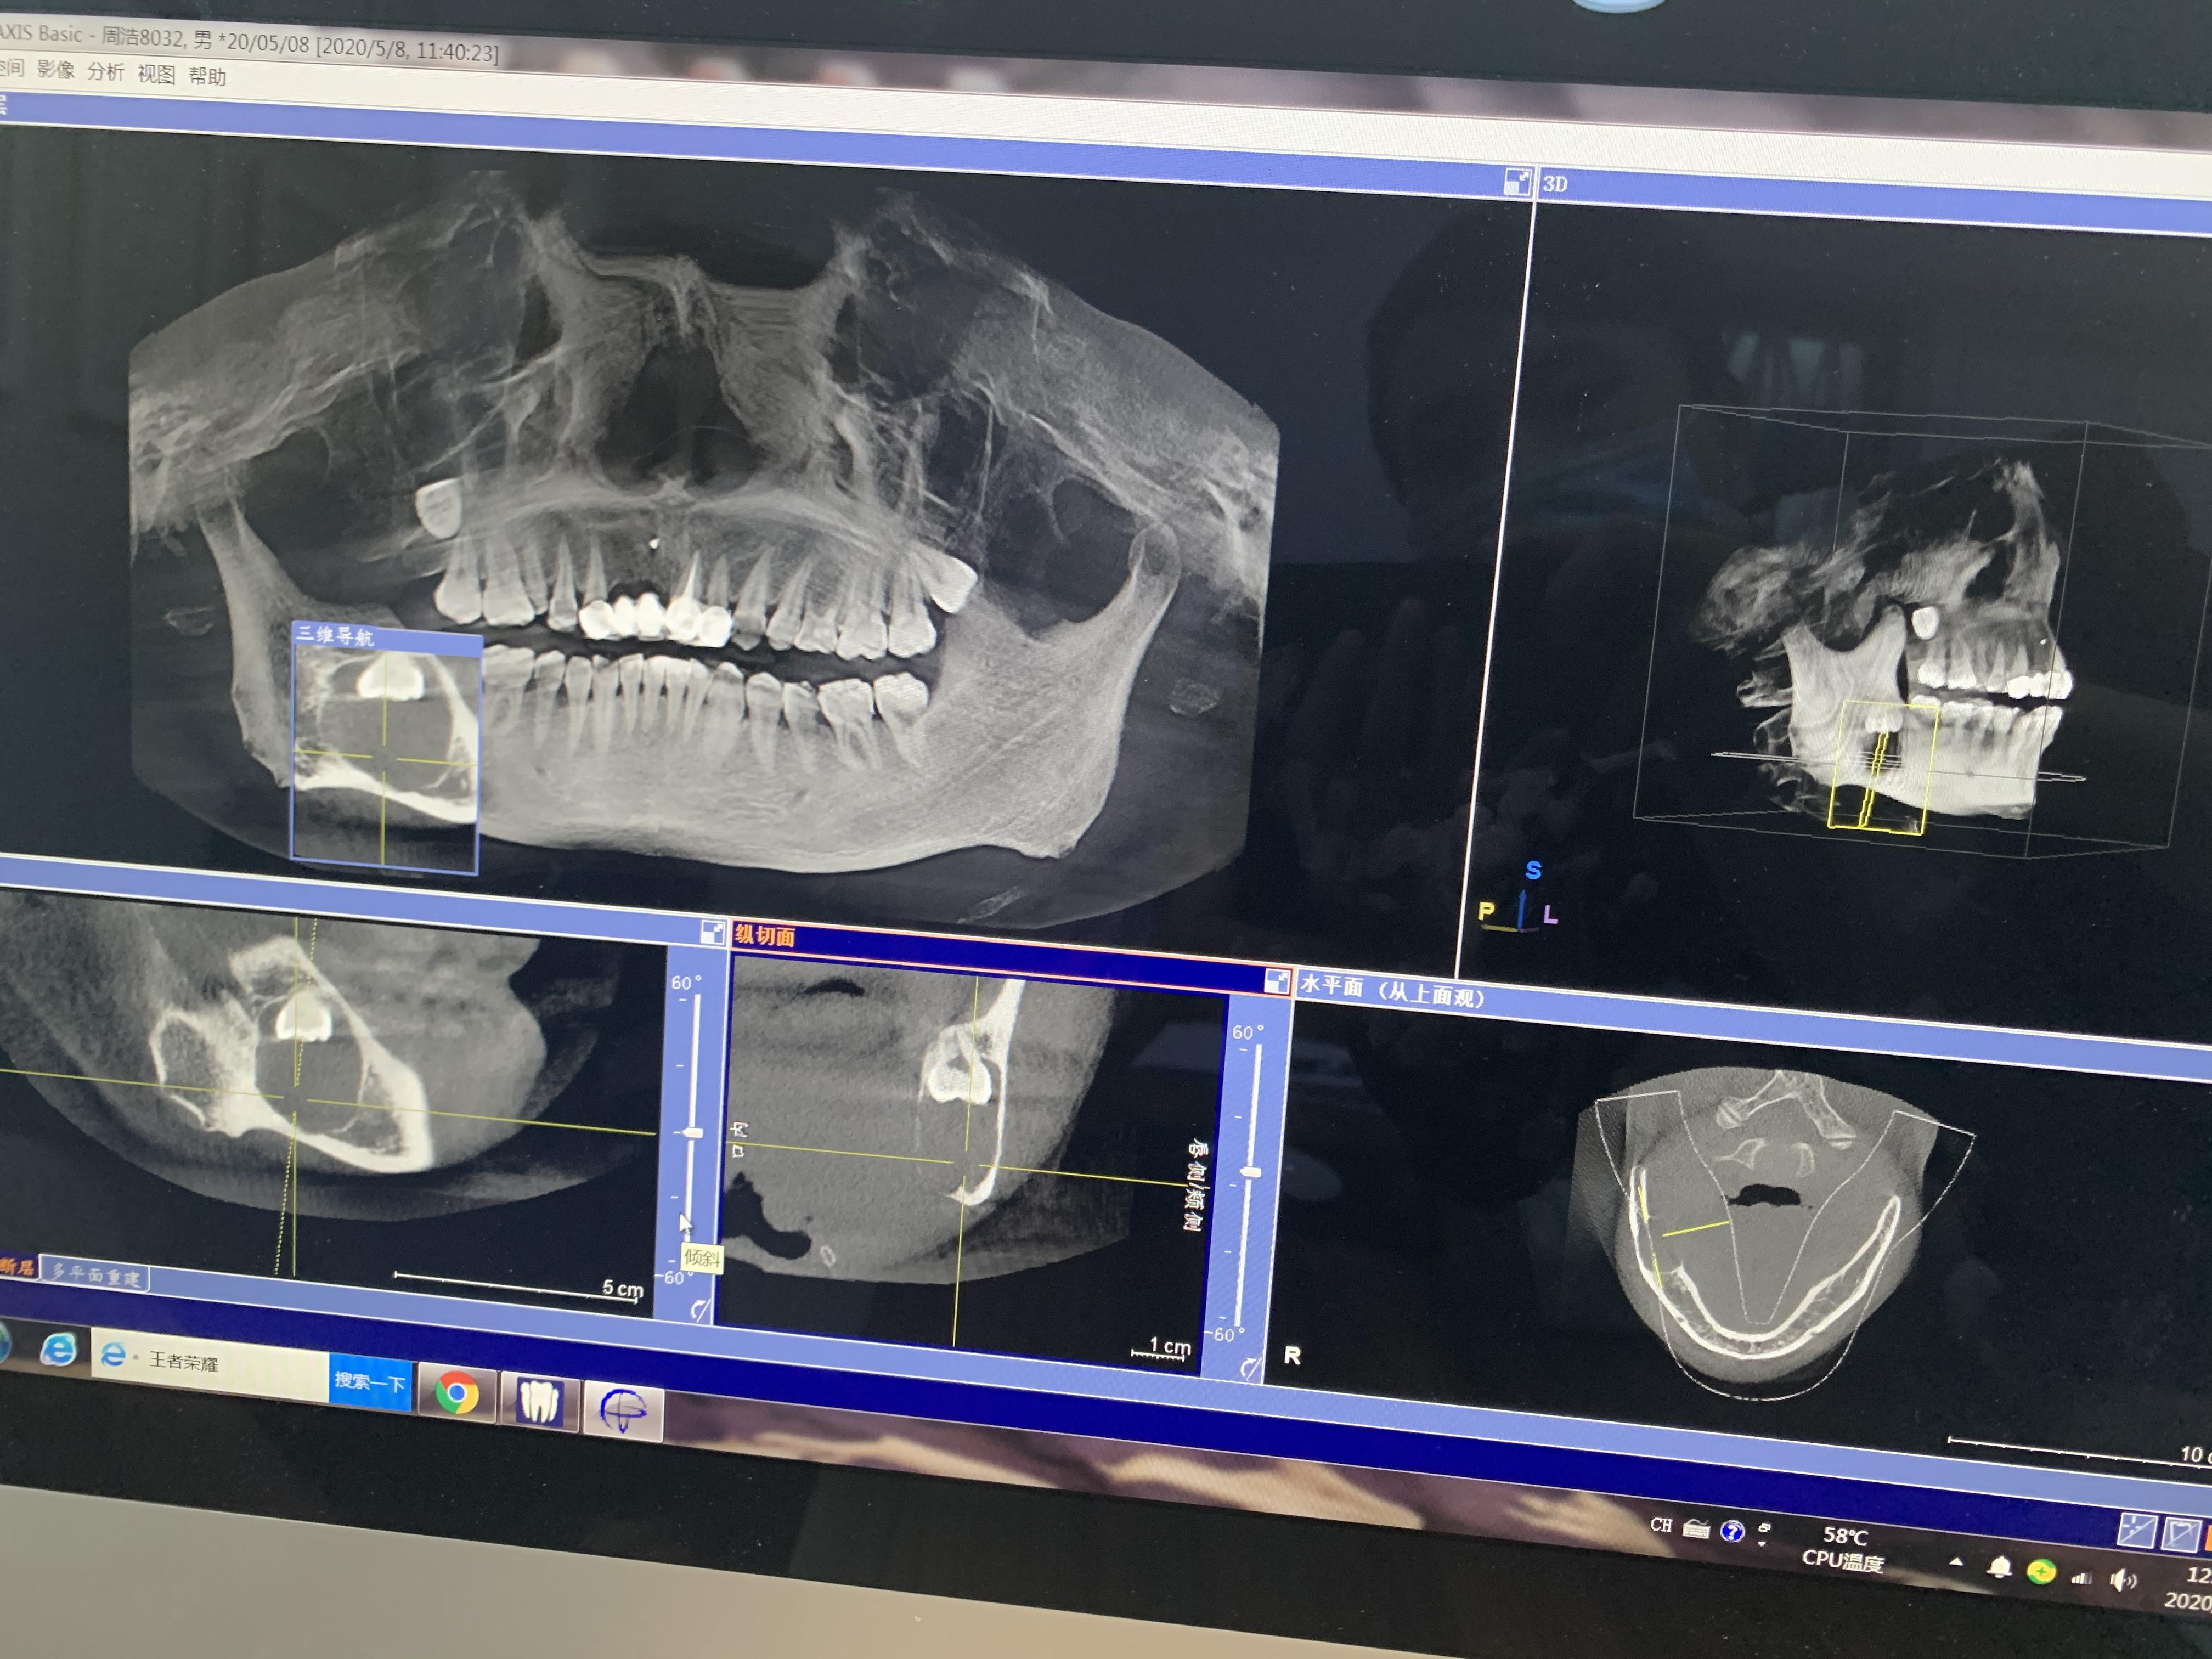

方框內(nèi)圓形的就是囊腫,從邊緣看,骨頭已經(jīng)很薄了

右下頜囊腫,倒阻生牙

下午1點(diǎn)半,片子拍好拿到了,王醫(yī)生看過(guò)后告訴我:

1.根據(jù)片子來(lái)看,囊腫確實(shí)挺大,神經(jīng)已經(jīng)被壓迫到一邊了,做完手術(shù)后右下巴和嘴唇會(huì)出現(xiàn)麻木的情況,當(dāng)然,這種情況后面也會(huì)慢慢恢復(fù),但每個(gè)人的恢復(fù)情況不一樣,所以不敢說(shuō)多久可以恢復(fù);

2.根據(jù)片子來(lái)看,可以不做開(kāi)窗,開(kāi)窗很多時(shí)候也是為了保護(hù)囊腫邊上的牙齒不用做拔除,但你囊腫位置不影響周圍牙齒,所以可以在手術(shù)中拔出阻生牙和囊腫刮治;